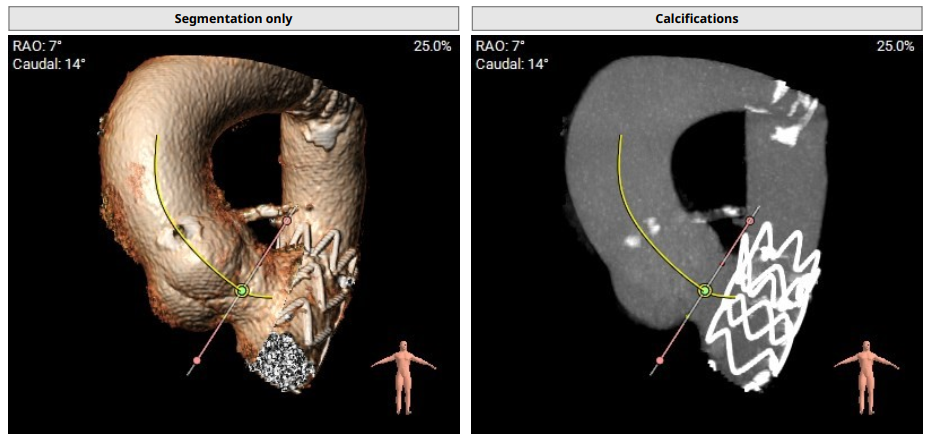

术前影像评估提示,患者为三叶瓣结构,瓣窦分布略显不均,但整体形态规则,无明显钙化负荷。主动脉瓣环直径29.0mm,左心室流出道直径28.5mm,STJ直径34.9mm,升主动脉直径37.9mm,冠脉开口高度充足(左冠17.8mm,右冠17.0 mm)梗阻风险低。

CTA评估(上下滑动查看更多照片)